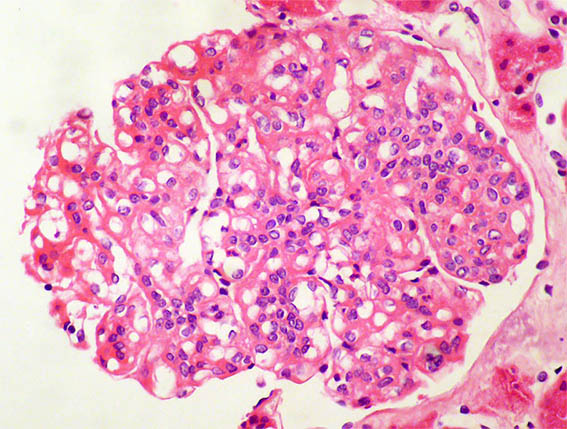

Figure 1. H&E, X400.